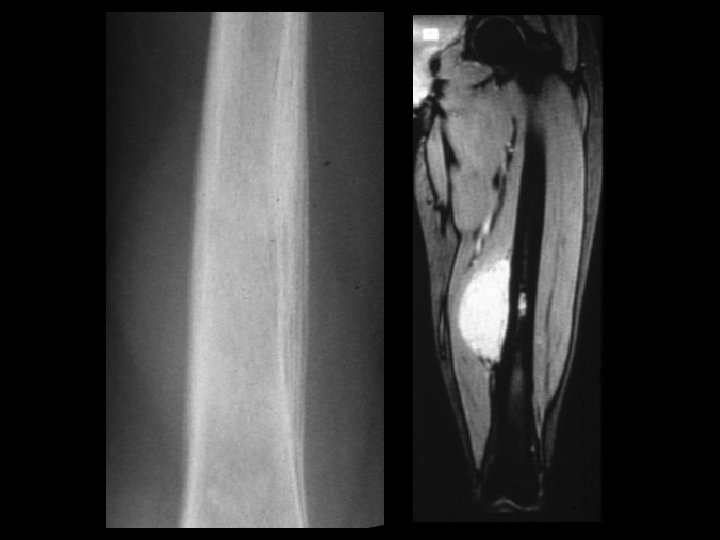

Langerhan’s cell histiocytosis • Findings: – Predominantly lytic lesion of the tibia with cortical thickening, periosteal reaction, and soft tissue swelling and edema • ddx: – Infection – Ewing’s sarcoma – Lymphoma